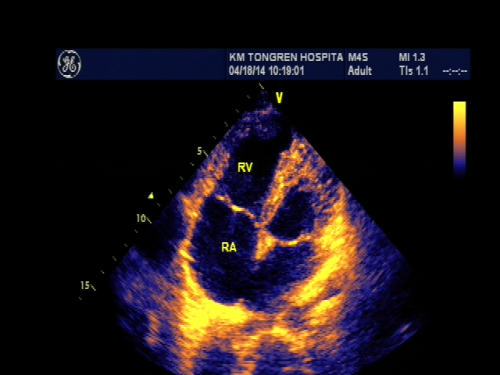

心脏超声是用超声波显示心脏、血管结构的一种检查方法,它分为M型超声、B型二维超声,三维立体超声。心脏超声由声波来探测血流状态和速度,还有彩色心脏超声由彩色血流的方向、压差表现不同的色彩变化,而知道病灶或异常构造的所在。此方法安全,没有放 射性,诊断准确率高,对病人没有痛苦和损伤,价格相对便宜,检查结果迅速及时,可反复多次检查,对很多心脏病的诊断有帮助。

动脉导管未闭